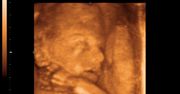

Zdjęcia płodu

Zdjęcia płodu - twarze